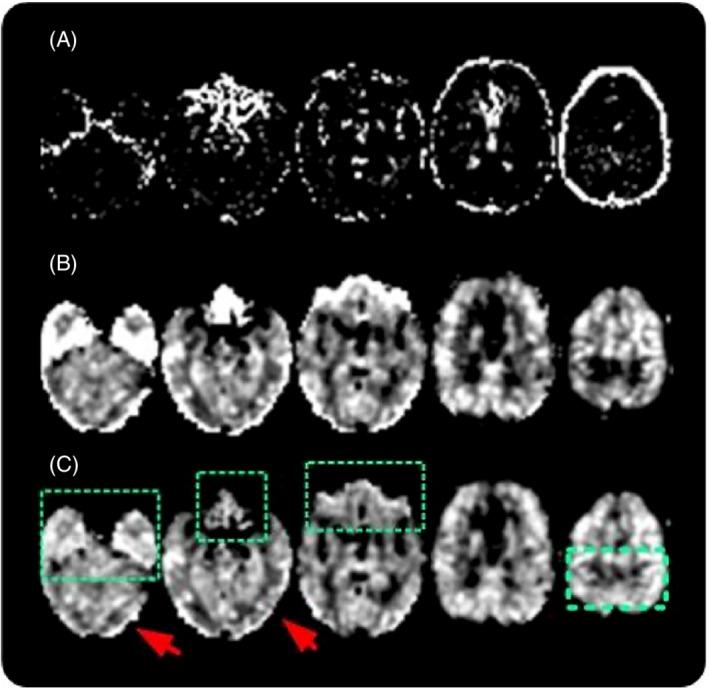

This review article provides an overview of a range of recent technical developments in advanced arterial spin labeling (ASL) methods that have been developed or adopted by the community since the publication of a previous ASL consensus paper by Alsop et al. It is part of a series of review/recommendation papers from the International Society for Magnetic Resonance in Medicine Perfusion Study Group. Here, we focus on advancements in readouts and trajectories, image reconstruction, noise reduction, partial volume correction, quantification of nonperfusion parameters, fMRI, fingerprinting, vessel selective ASL, angiography, deep learning, and ultrahigh field ASL. We aim to provide a high level of understanding of these new approaches and some guidance for their implementation, with the goal of facilitating the adoption of such advances by research groups and by MRI vendors. Topics outside the scope of this article that are reviewed at length in separate articles include velocity selective ASL, multiple-timepoint ASL, body ASL, and clinical ASL recommendations.